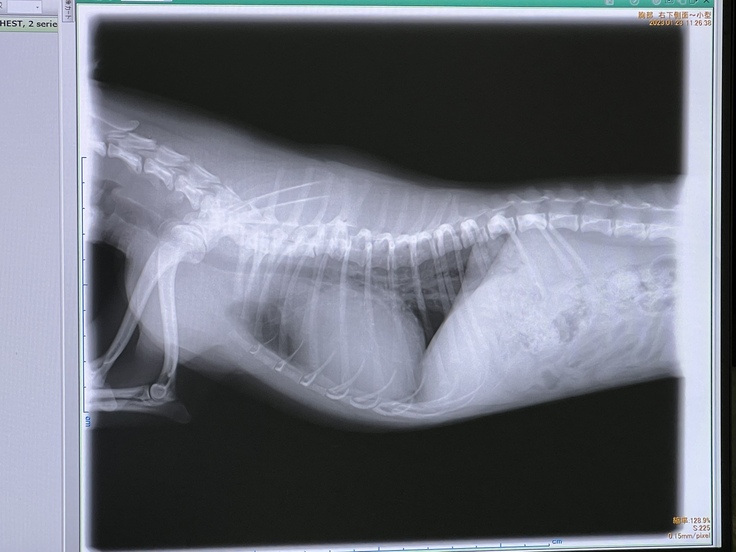

素人の私でもハッキリ分かるくらいレントゲンに写った心臓もかなり肥大しており早期の手術を勧められました。このままだと三尖弁まで影響が出て腹水が溜まり呼吸困難になりやがて死に至ります。今飲ませているお薬はすぐ止めて下さいと。

心臓を止めて人工心肺を使った手術で正午12時から16時の4時間の手術である事と10日間の入院になりますと。レントゲンで心臓がかなり肥大しているのが分かります。